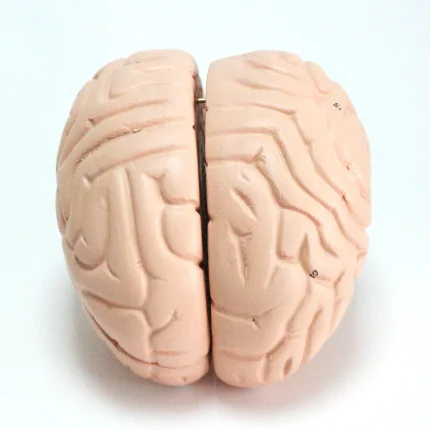

Modèle anatomique de cerveau humain

Modèle de cerveau humain

4 parties : (Fabriqué à partir de fibre de verre)

Modèle anatomique de cerveau humain

4 parties : (Fabriqué à partir de fibre de verre)

Ce cerveau est médialement divisé en deux parties, la moitié droite peut être démontée en frontal avec les lobes parentaux, le tronc cérébral avec les lobes temporaux et occipitaux en deux parties. Placé sur une base amovible avec Key Card numérotée.